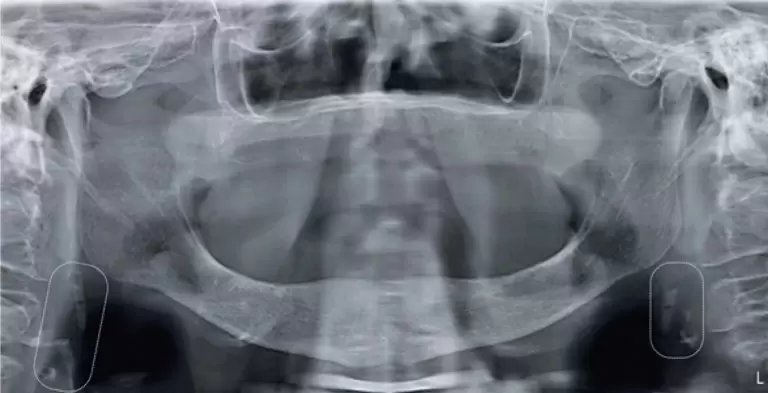

A 49-year-old man came to our emergency department with a 2-day history of fever, cough, anosmia, ageusia and odynophagia. His past medical history included hypertension. At the time of this presentation, chest computed tomography revealed peripheral and bilateral ground-glass opacities, with some visible intralobular lines – typical findings of pneumonia caused by the severe acute respiratory syndrome coronavirus 2 (SARS-CoV-2). In addition, some findings revealed the target sign (). The patient’s supportive treatment was continued, and reverse-transcriptase polymerase chain reaction […]